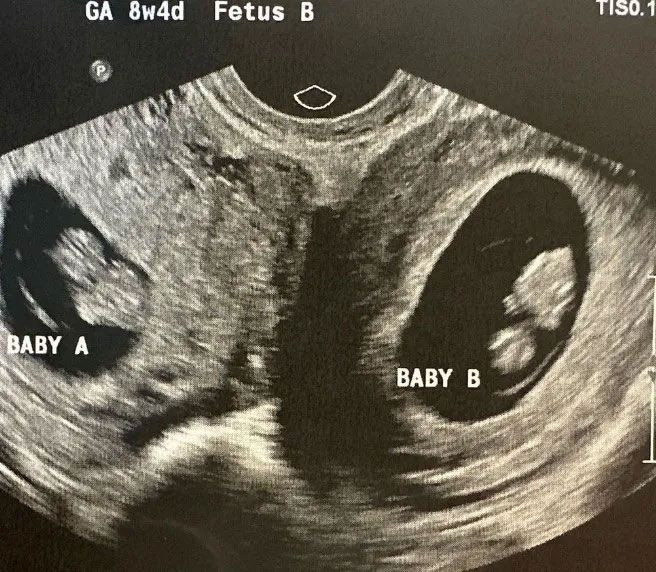

ABD'nin Alabama eyaletinde yaşayan 32 yaşındaki çift rahimli üç çocuk annesi Kelsey Hatcher, tıp dünyasını şaşkına çevirdi. Çünkü kadının her iki rahminde de birer bebek var.

ABD'nin Alabama eyaletinde yaşayan çift rahimli bir kadının, iki rahminde de bebek taşıdığı görüldü. Doktorlar bunun "çok şaşırtıcı ve nadir" olduğunu ifade etti.

32 yaşındaki üç çocuk annesi Kelsey Hatcher, iki rahimle doğdu. Hatcher'ın bu durumu bahar aylarında iki rahminde de bebek taşıdığına kadar bilmediği belirtildi.

Çift rahimlilik kadınların yaklaşık yüzde 0.3'ünde görülüyor. Araştırmalara göre anormallik embriyoda gelişimin çok erken aşamalarında meydana geliyor.